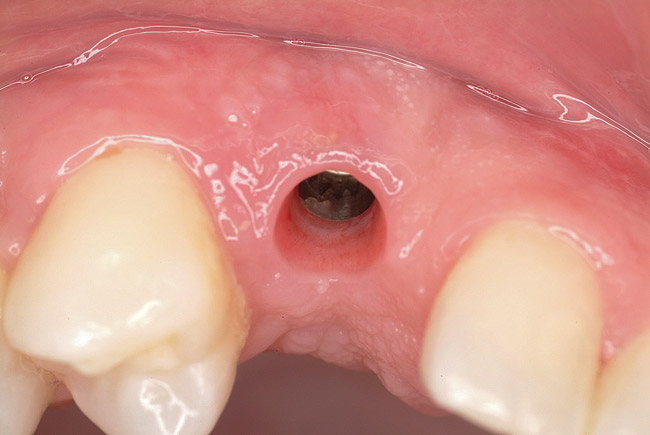

Figure 8  Primary stability of the implant achieved, facilitating a transmucosal healing approach.

Figure 8

Figure 9  Primary stability of the implant achieved, facilitating a transmucosal healing approach.

Figure 9

Approximately 4 months after grafting, the patient returned for clinical and 3-D radiographic evaluation. The thinnest area of ridge width preoperatively was remeasured in approximately the same location, demonstrating a gain of about 4 mm (Figure 7). The treatment plan was to place a 3.5-mm x 13-mm implant with a computer-generated guide (SiCat, Sirona Dental, www.sironausa.com), eliminating an additional open surgical procedure. Planning included initial osteotomy preparation with single-use drills combined with a localized ridge expansion using narrow, tapered osteotomes. This was performed approximately 5 months after the augmentation procedure, achieving primary stability of the implant, facilitating a transmucosal healing approach (Figure 8 and Figure 9). Following each step of osteotomy preparation, a probe was inserted along the walls of the site to confirm the integrity of the buccal and palatal walls prior to implant insertion.